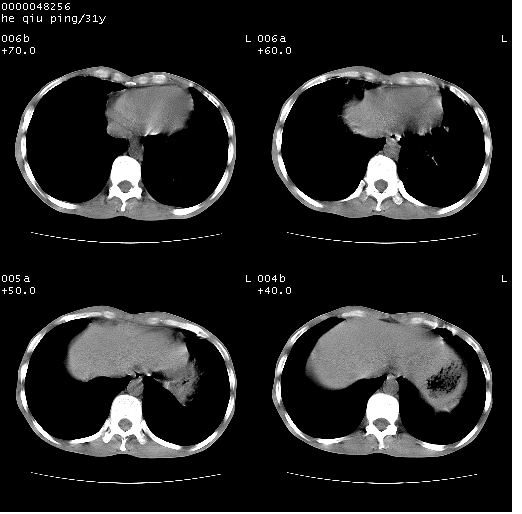

标题: CT13402:M,31Y。肺结核伴空洞形成?

咳嗽半月余,消瘦体质,呼吸音弱。无其他病史。cr:肺转移瘤待。

双上肺多发空洞,双飞散在分布大小不一的片状结高密度影节状大片状高密度影。符合结合肉芽肿形成及空洞形成。

双侧弥漫性病变,双上叶尖后段、下叶北段见多个空洞,多见于结核感染。右中叶及双下叶斑片状,结节状影,考虑为肉芽肿形成及支气管播散。但由于患者消瘦体质,抵抗力低下,若继发感染,如金葡菌肺炎也有可能。